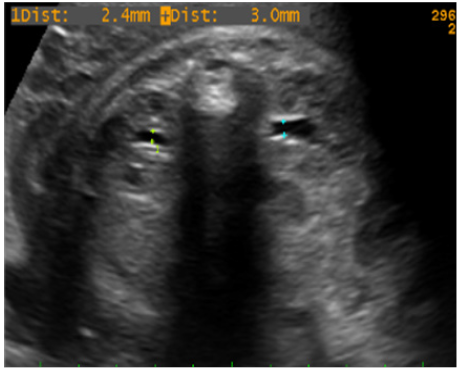

El diámetro máximo anteroposterior de la pelvis renal fetal se midió utilizando transductor convex multifrecuencial para estudios transabdominales (3-5 Mhz), con un equipo de alta resolución Easote My Lab. Se utilizó la capacidad del equipo para freeze y cine-loop para encontrar los puntos de reparo ultrasonográficos y realizar las medidas de manera correcta siguiendo el método estándar: a través de un corte transversal del abdomen fetal bajo visualizando ambos riñones a cada lado de la columna vertebral, se identifica la pelvis renal que aparece como una imagen central anecoica, tubular con paredes ecorrefringentes. La imagen obtenida es entonces congelada y magnificada de modo que ocupe toda la pantalla y se medirá la distancia anteroposterior de la pelvis renal tanto derecha como izquierda expresada en milímetros, de borde interno a borde interno y perpendicular al eje máximo de la zona econegativa (Figura 2 y 3).